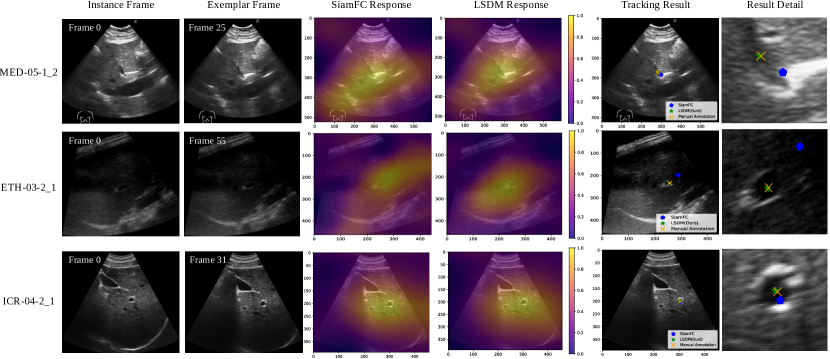

Refer to caption

Figure 1: Illustration of ultrasound medical landmark under different challenges. From top to bottom: tracking under landmark deformation, acquisition noise, visual ambiguity and partial observation. From left to right: reference frame, example target frame, cropped region with LSDM (green) and baseline SiamFC (yellow) tracking results.